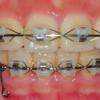

[치아교정후기22] 교정만의 오라픽스 치아교정후기

[치아교정후기22] 교정만의 오라픽스 치아교정후기 안녕하세요 여러분~ 벌써 한달이 지...

[치아교정후기21] 교정만의 오라픽스 치아교정후기

[치아교정후기21] 교정만의 오라픽스 치아교정후기 안녕하세용!!! 21화 치아교정후기에...

[치아교정후기20] 교정만의 오라픽스 치아교정후기 - 고무줄고무줄고무줄

[치아교정후기20] 교정만의 오라픽스 치아교정후기 - 고무줄고무줄고무줄 안녕하세요~ ...

[오라픽스 치아교정후기 19] 교정만의 치아교정후기 - 발치공간이 줄어들 때까지...

[오라픽스 치아교정후기 19] 교정만의 치아교정후기 - 발치공간이 줄어들 때까지... 안...